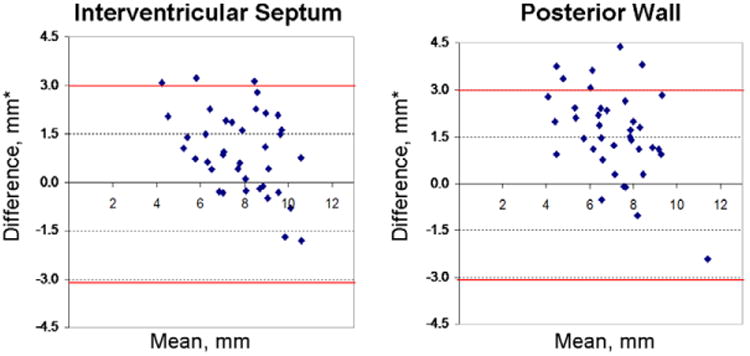

Figure 1.

Agreement between echocardiographic and cardiac MRI (CMR) measurements of septal and posterior left ventricular (LV) wall thickness. Bland–Altman plots demonstrate that echocardiographic (echo) measurements were usually greater than CMR measurements. The red lines depict 2 SDs from the mean difference between echo and CMR measurements. *Difference between mean echo and CMR measurements of wall thickness. Mean=average of the echo and CMR measurement of LV wall thickness.

Comparison of LV Wall Thickness Determination by Echo Versus CMR

Figure 1 illustrates the moderate agreement between echo and CMR LV wall thickness measurements. Intracluster correlation coefficients were 0.62 for the IVS and 0.34 for the PW. CMR LV wall thickness measurements were on average ≈19% lower than echo. Of 40 subjects, both echo and CMR categorized 36 as without hypertrophy (LVH−), indicating clinical diagnostic agreement of 90% between these 2 modalities. In 3 of 40 subjects (7.5%), CMR detected mild, focal hypertrophy (measuring 13.1–13.9 mm) that did not reach the defined threshold for LVH and diagnosing HCM (13 mm) by echo. Subject 4 had borderline LVH by CMR (MWT=12.6 mm) that was just under the defined LVH threshold by echo (MWT=11.9 mm; Figure 2; Table 3). Echo and CMR were performed on the same day for these 4 subjects. In discordant subjects, the mean difference between CMR and echo measurements of maximal LV wall thickness was 1.9±1.2 mm (range, 0.7–3.5 mm). Table 3 also lists other subtle abnormalities present in these 4 subjects, including low global Ea velocities and mild ECG abnormalities.